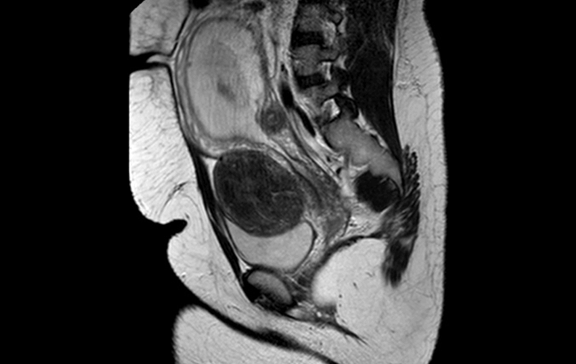

A 30-year-old female with suspected recurrent ovarian granulosa cell tumor in pregnancy. Contrast-enhanced sagital MRI image showing large predominantly isotense pelvic mass measuring 8.9 cm x7.1 cm. Areas of hypointensities within it with correlating hyperintensities likely due to cystic changes appears seperae from the uterus. (A: pregnant uterus, B: mass, C :bladder). (Page 167)